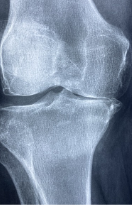

연골은 부드러운 움직임을 위해 뼈 사이에 존재하는 결합 조직으로 인간의 근골격계를 구성하는 중요한 요소 중 하나입니다. 연골은 충격을 흡수하고 뼈 마찰을 줄여 관절 부상을 예방합니다. 또한 연골은 관절에서 분비되는 활액에 영양분을 공급받아 영양분을 흡수해 생존한다. 그러나 나이가 들어감에 따라 연골 조직이 퇴화하고 내구성과 탄력성이 떨어지게 되어 관절염과 같은 상태로 이어질 수 있습니다.

- 소음: 무릎을 움직일 때 불편한 딱딱거리는 소리가 들릴 수 있습니다. 이것은 무릎 연골 손상 후 뼈 마찰에 의해 발생합니다.

- 무릎 안정성 감소: 무릎 연골 손상은 무릎의 안정성을 감소시킬 수 있습니다. 무릎의 근육, 인대, 연골 손상으로 인해 발생합니다. 이러한 부상은 무릎 불균형, 충격 및 무릎 움직임의 불균형으로 이어질 수 있습니다.

무릎은 몸을 지탱하고 움직이는 중요한 역할을 합니다. 이러한 기능을 수행하는 것은 힘든 작업이며 이러한 기능을 수행하는 무릎 관절은 매우 복잡합니다. 따라서 무릎은 가장 취약한 부위 중 하나입니다. 무릎연골손상은 무릎관절에 연골손상이 발생하는 상황입니다. 이는 여러 가지 이유로 발생할 수 있습니다.